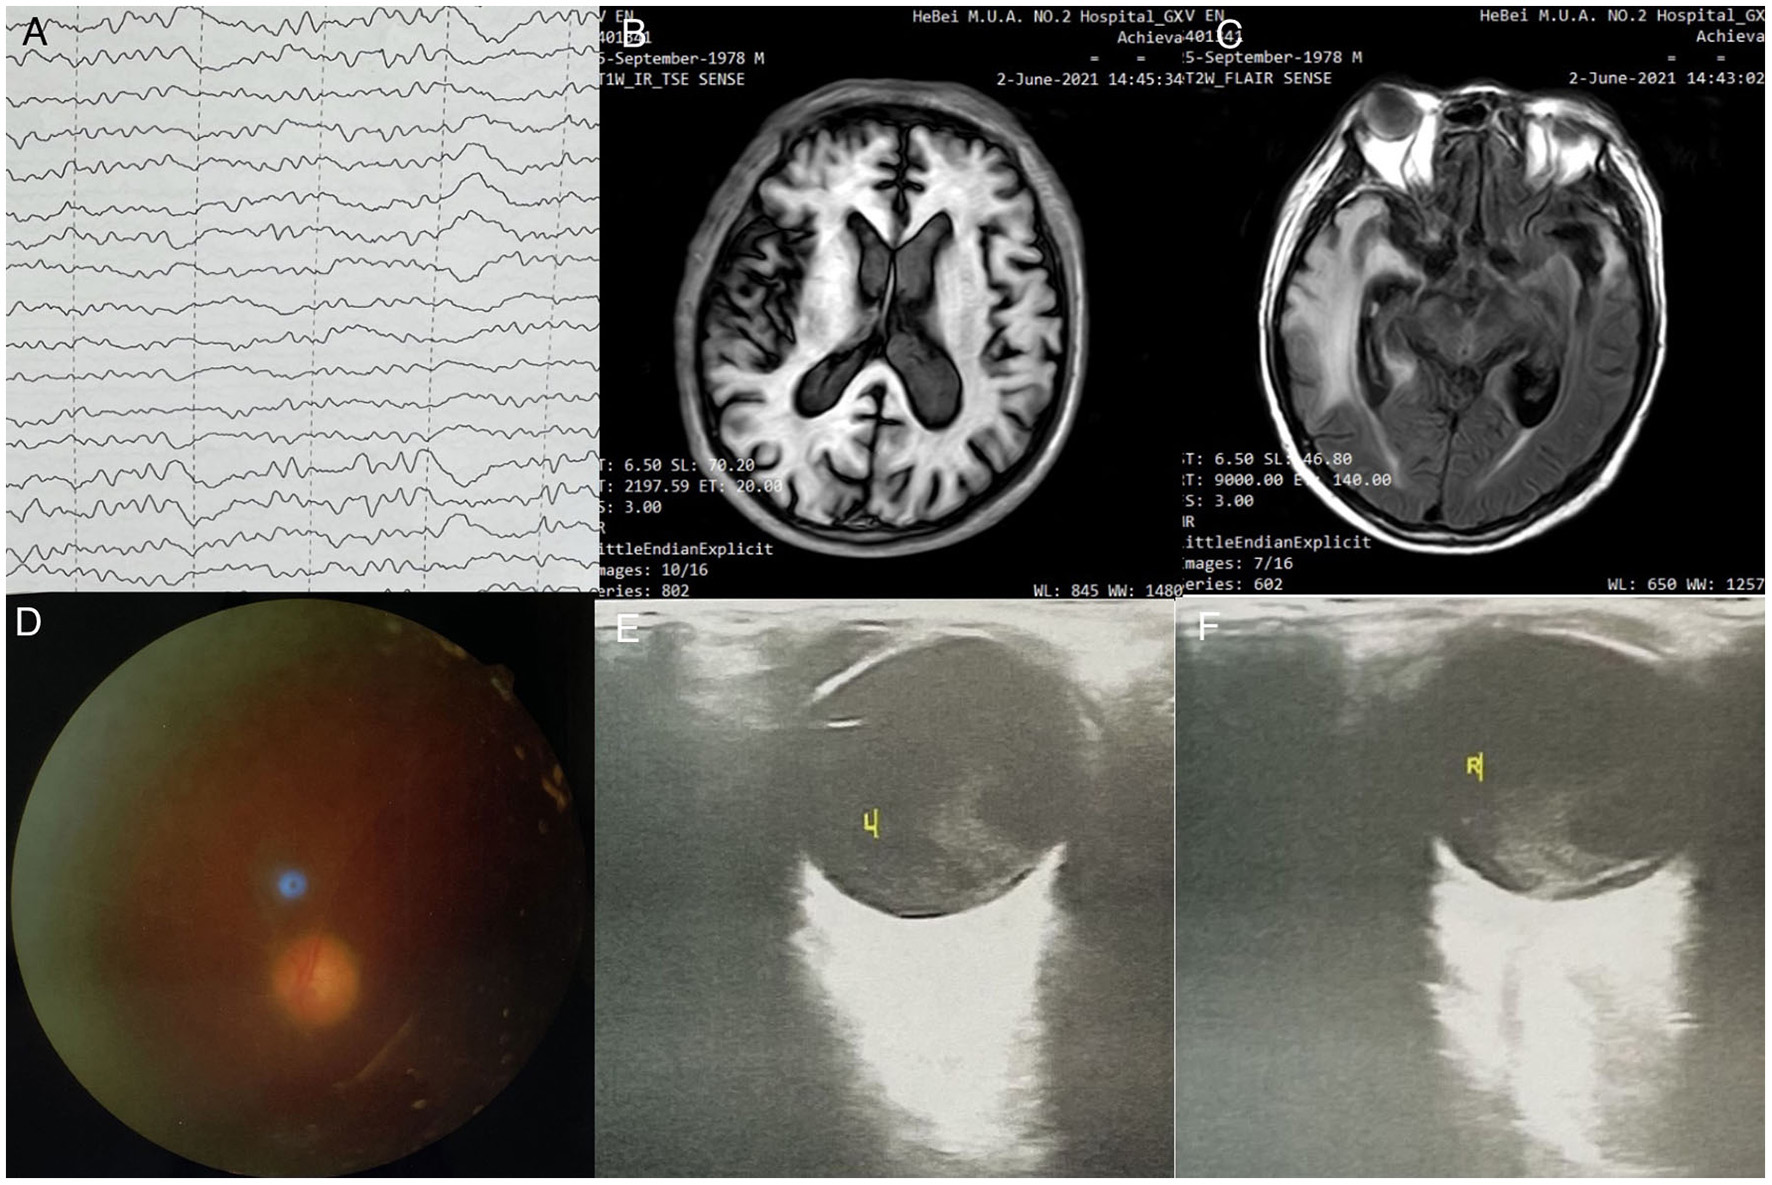

Figure 1. (A) Electroencephalography findings: Severe abnormal diffuse mixed slow waves with a lot of fast waves, intermittent low-voltage waves, lasting about 1s, diffuse 1-2Hz irregular s activity, left sharp waves and sharp slow waves are emitted from the front side of the head; (B) Head MRI - T2 FRFSE: Bilaterally symmetrical abnormal signals are observed in the anterior cingulate gyrus; (C) Head MRI - T2 FLAIR sequence: Symmetrical abnormal signals of insula and fronto temporal lobes; (D) Fundus examination: Both eyes have clear cornea with no hyperemia, anterior chambers, pupil diameter of ~3mm, slow reflection of light; (E) Ophthalmic ultrasound-L: (1) Severe vitreous opacity; (2) Thickening of the posterior wall of eyeball; (3) Thickening of the four rectus muscles of the eyes; (F) Ophthalmic ultrasound-R: (1) Severe vitreous opacity; (2) Thickening of the posterior wall of eyeball; (3) Thickening of the four rectus muscles of the eyes. The ring of the right eye is intact, the lens wave is visible, and the dark area can be seen in the vitreous body. There is medium to high amount of diffuse flocculent weak echo and cluster echo. The posterior wall of the ball is thickened and slightly rough. The thickness of the superior rectus, external rectus, inferior rectus, and medial rectus is ~5.9, 5.6, 5.6, and 6.4mm, respectively.

Figure 3. (A) EEG examination: moderate to severe abnormal EEG, background diffuse 0, 6 slow wave bursts, 7-8 Hz slow rhythm bursts in the occipital lobe; (B) Head MRI - T1IR-TSE: normal head size, bilateral frontal lobe, temporal lobe, insula, bilateral hippocampus, bilateral thalamus, bilateral cingulate gyrus, flaky T1 low signal; (C) Head MRI - T2 FLAIR sequence: head size is normal; temporal lobe, insula, and bilateral hippocampus present high signal in T2 FLAIR, high signal in FLAIR; local sulci are clearer than before; (D) Fundus examination-left eye; (E) Ophthalmic ultrasound-L: severe vitreous opacity, mild thickening of the posterior wall of the eyes; (F) Ophthalmic ultrasound-L: severe vitreous opacity, mild thickening of the posterior wall of the eyes, thickening of the inner rectus muscle of the right eye.